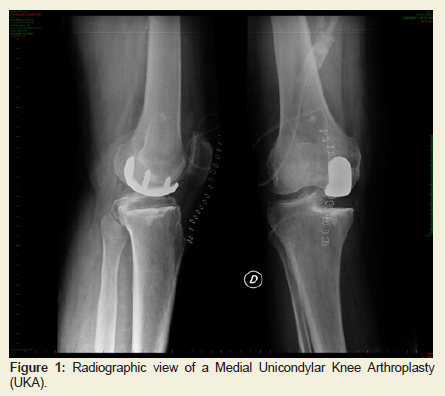

The study cohort consisted of 246 patients (men/women: 87/159),who underwent 266 medial UKAs. UKAs were implanted in 187 patients (70.3 %) for osteoarthritis isolated to medial compartment and in 79 (29.7 %) for primary osteonecrosis of medial femoral condyle. Selection criteria were: patients more than 50 years old, involved in low-demand activity, with a BMI less than 35 kg/m2, a knee ROM of at least 90 degrees, less than 10 degrees of fixed flexion deformity, without clinical cruciate ligament instability and major angular deformities [30]. If the patient was involved in a high-demand activity, UKA was offered only if such activity could be curtailed after surgery. Inflammatory arthritis, secondary spontaneous osteonecrosis of the knee (SPONK) or involvement of other compartments were considered as contraindication for the procedure [9,30-32].Preoperatively, all patients had weight bearing anteroposterior and lateral radiographs of the knee [33]. The UKA’s were all performed by three senior surgeons (MM, SZ, FI) through a minimally invasive, quadriceps-sparing surgical exposure [34-36], using a surgical technique recommended by the manufacturer, to implant the cemented femoral and all-polyethylene tibial components (Preservation® Uni-Compartmental Knee; DePuy Orthopaedics Inc, Warsaw, IN, USA) (Figure 1). The size of the all-poly tibia component used was selected and applied in order to restore the presumed prepathological varus deformity [37]. As estimated from the contra lateral limb.